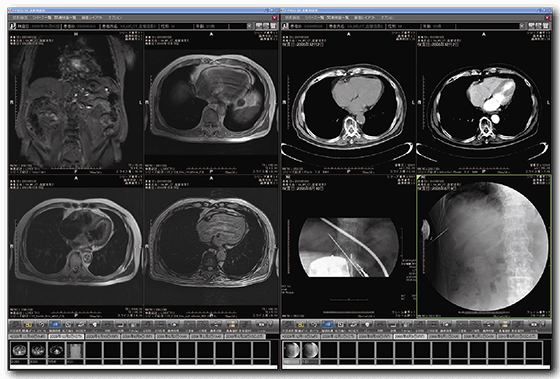

画像ハンドリング機能

画像展開は、過去画像・レポートも含めた独自の画像ハンドリングロジックを採用し高いパフォーマンスを実現。

各種読影用機能が組み合わされ、快適な読影環境を創りだします。

比較読影モード:

同一モダリティ、同一部位の検査が自動展開されます。 またモニタ構成に応じて、手動展開に切り替え、ボタン一つで過去画像を展開させることも可能です。

フリーレイアウト機能:

マウスのドラッグ操作のみで関連検査や異なる検査機器の画像、別患者の症例を同一画面上に表示することが可能です。 症例の比較や、正常例を表示してご説明するケースなど、様々な場面に応用することができます。

ハンギングプロトコル設定:

DICOM TAGにある、検査種別や部位、検査記述などの情報を基にコマ割りや表示順を設定することができます。 ルーチンとなる操作手順を自動化することで、読影の効率化を実現します。